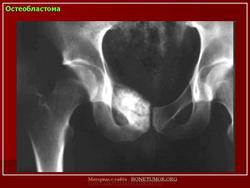

Остеобластома

Рентгенологическая картина остеобластомы представляет литический или смешанный, четко очерченный округлый или овальный дефект целостности кости с периостальной реакцией и зоной реактивного костеобразования.